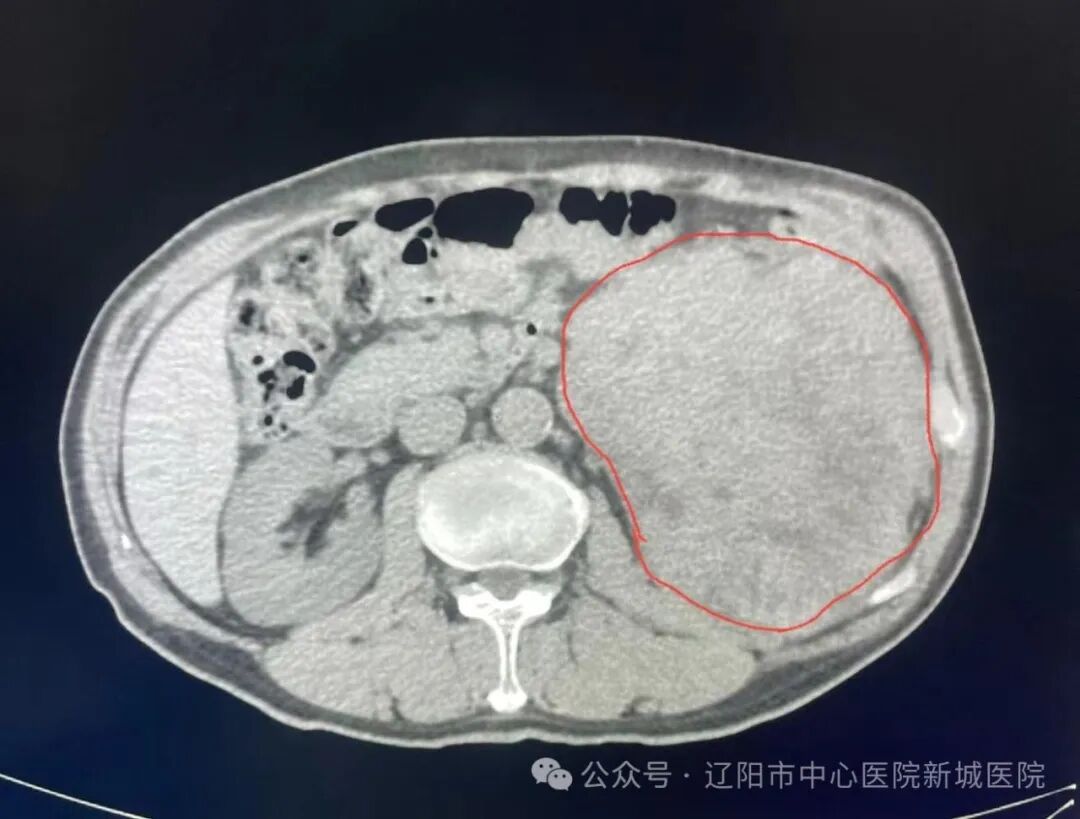

2月5日,已臨近春節(jié),新城醫(yī)院泌尿外科收治了一位中年男性患者,病因是他在家里整理重物時,突然感到腰部劇痛,肢體不能活動。CT檢查提示:腰椎陳舊性骨折,左腎區(qū)巨大占位15cm×13cm,患者緊急辦理了入院手續(xù)。

病患腎臟圖片

泌尿外科主任陳余糧會診后,考慮患者腎癌的可能性大,腰部巨大腫物隨時有破裂風險,如腫物破裂會出現(xiàn)大出血,將危及患者生命,必須馬上手術(shù)。陳主任與主治醫(yī)生立即與家屬耐心講解該病目前的危急性、風險性。

如果剝離瘤體造成血管神經(jīng)損傷,將會產(chǎn)生術(shù)中大出血;如果剝離瘤體破梨,將會污染腹腔,產(chǎn)生癌細胞腹腔種植,患者預后將大打折扣。陳主任帶領(lǐng)醫(yī)療團隊精心細致為患者手術(shù),歷時3個小時,終于將15cm×13cm的巨大腫物完整移出腹腔,患者安返病房(術(shù)后病理提示腎透明細胞癌)。